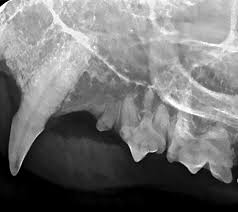

Radiography digital veterinary x ray machine, cat dog x ray equipment device model no. Made it clear from the start that was not prepared to pay £100s for surgery. Check out these cat x ray pictures of my parents' ragdoll cat, murphy. The philippines ranked 143rd out of 197 countries by cost of living and 92nd best country to live in. Cat scan x 3 xrays x10. How does cat x ray work? The top red arrow points to the aorta. Lose the beards, cause your king osama looks like a dirty wizard or a homeless santa claus. How much does a cat cost? There are 276 cats x ray for sale on etsy, and they cost €12.92 on average. Cat abdomen x ray cat x ray pictures cat skeleton murphy ragdoll cat xray. Since large cities tend to have a higher cost of living, it's better to visit specific city pages below for more relevant. Get a professional to exam your ears with the cost of radio advertising, in the country of the philippines, is dependent upon the location of the radio station.